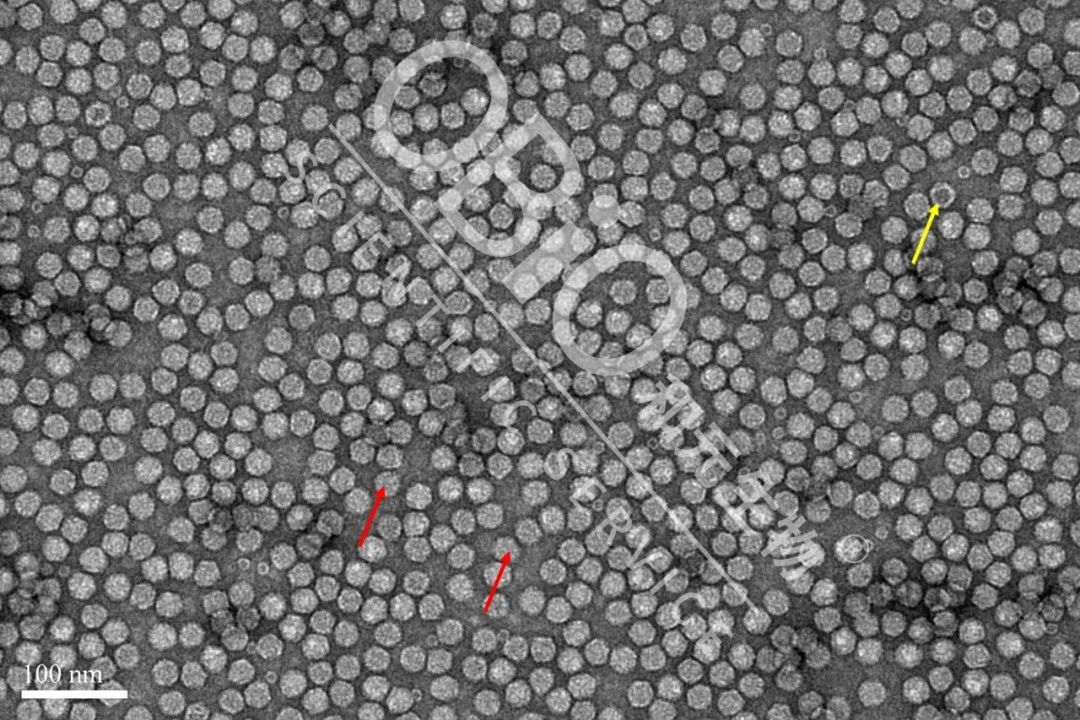

图3 至尊国际·(中国)至尊服务,至尊享受 rAAV载体生产空壳率

电镜结果:包装DNA基因组的病毒颗粒为实心颗粒(红色箭头);空病毒颗粒中间存在空洞(黄色箭头)